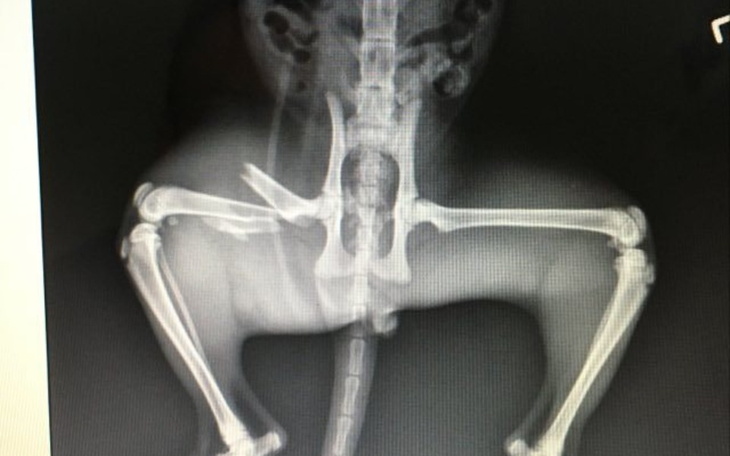

Łatek - najbardziej towarzyski z ekipy, pomieszkiwał w okolicy, później u nas na podwórku, był dokarmiany razem z dwójką a wcześniej trójką rodzeństwa. Jednego udało się wydać, pozostałe 3 do wczoraj czekały na nowe domy. Z racji, że mamy inne zwierzęta, nie mogliśmy ich do zabrać do siebie, ale dwa razy dziennie meldowały się na jedzenie w komplecie mieszkając na podwórku. Wczoraj ( 23.09) Łatek nie dotarł na śniadanie, a na kolację ledwo się pojawił i jak się okazało ma złamaną nogę... Nie wiadomo co się stało, ale pomóc trzeba... Chwilowo Łatek rezyduje w łazience... Koszt operacji ok 1000zł, plus wizyty po, gips itp... Koszty do teraz to 200zł ( rtg, znieczulenie, zastrzyki) Aktualnie radzi sobie nieźle, ale mimo wszystko złamana noga wisi... Zrzutek jest dużo, ktoś powie, że lepiej taką kwotę przeznaczyć dla ludzi i może racja.... ale liczymy na to, że znajdzie się ktoś kto wpłaci i na kogoś potrzebującego i na Łatka... Łatek po remoncie będzie prawdopodobnie do wzięcia, także można traktować wpłatę jako inwestycję :) Ew. do dwóch największych wpłat szczęśliwiec dostanie kotka w prezencie:) Czarny to kotka, ciapaty- kotek. Koty udało się wysterylizować, są towarzyskie. Jeśli się uda zebrać więcej niż koszty leczenia, wpłacimy na schronisko albo kocią fundację czy co tam innego będzie w potrzebie.